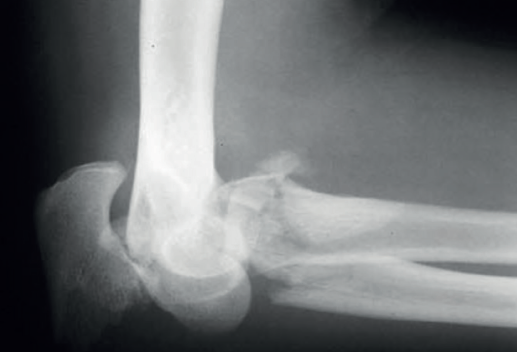

El siguiente patrón de inestabilidad tiene lugar tras una caída hacia atrás con el brazo extendido y provoca una inestabilidad en varo posteromedial. Se lesiona el LCL y se fractura la carilla anteromedial de la coronoides. En este tipo de lesiones, la cabeza radial típicamente no está fracturada.

Figura 2. Radiografía anteroposterior de una lesión que produce inestabilidad en varo posteromedial.